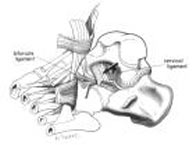

CTEV

Ctev3

Ctev4

Ctev6

Denisbrowne

Dennis Browne Splint

French osteotomy